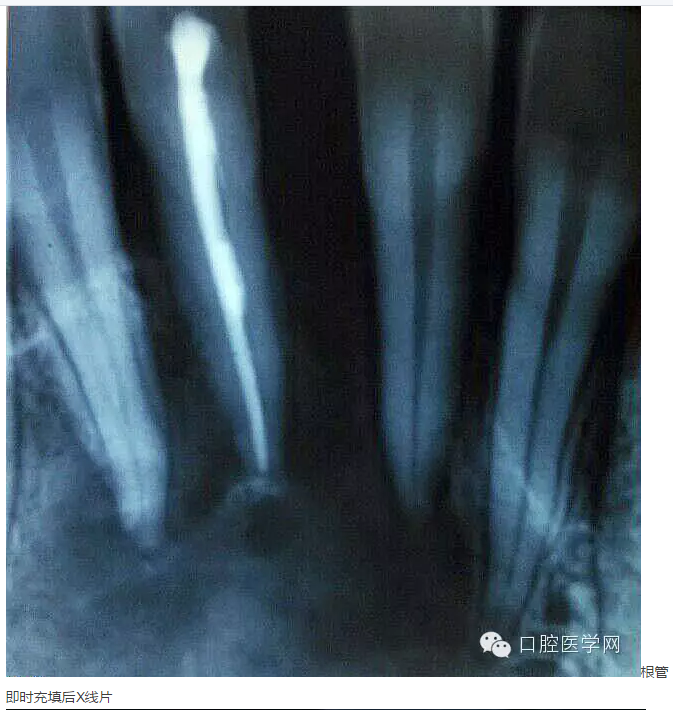

下面是一例 今年年初治療的下前牙根尖囊腫病例,患者因故未能按時復診,最近才來。